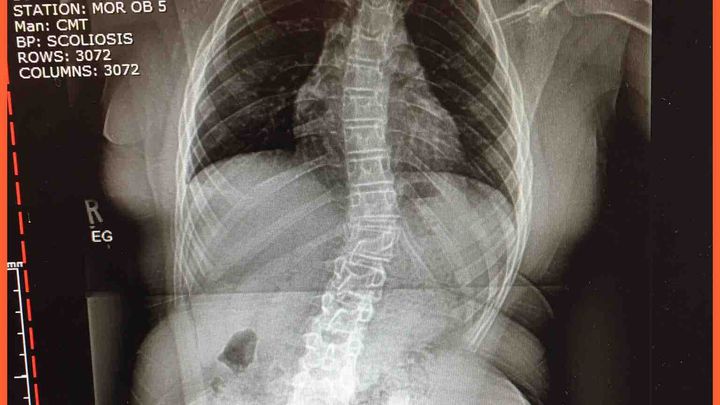

The  Warrior Princess is at it again.  She has been recovering from a broken femur for close to two years. During that time she had numerous surgeries and was diagnosed with severe scoliosis.  Not only does she have a lumbar curve she also has a thoracic curve.  We moved to Florida and it has taken 9 months to find a surgeon who would take her as their patient. I had taken her to 5 surgeons who all insisted that I go back home to the doctor who knew her the best. They were all afraid of causing her more problems and not being able to properly care for her. They wouldn't even release her for therapy.  After a conversation with her surgeon back home she suggested that I take Isabella to Miami to the Orthopedic Trauma Center. A few weeks ago I made the trip with her and met with Dr. Schoenleber and while consulting with him he called his colleague Dr. George to look at the xrays for Isabella's spine.  He called her scoliosis  "progressive" and changing quickly.  Her lower spine was at a 50% and thoracic at 45%, a 20% increase since February when she saw a scoliosis specialist closer to home.  He discussed a plan with me and Dr. Schoenleber agreed that before addressing her hips and leg (still healing from the break 2 years ago), that her back must be fixed. Isabella was scheduled for Scoliosis surgery on July 20th,  a week after her 12th birthday.  This will be a completely new surgery for her with new doctors.  Her hospital stay shouldn't be long but it really depends on how she does.  She will have bi weekly follow ups at first and then monthly.  She is expected to be back to 100% with in 6 months and Dr. Schoenleber will see her again at the 3 months mark to put a plan together for him surgery and hardware removal and replacement.